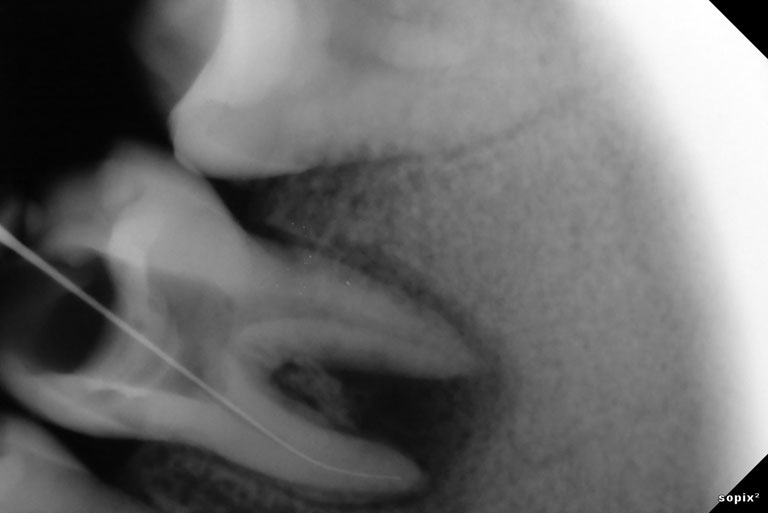

Root Canal Treatment Solution

Penanganan yang tepat dengan alat dan teknologi yang memadai menjadikan hasil yang optimal